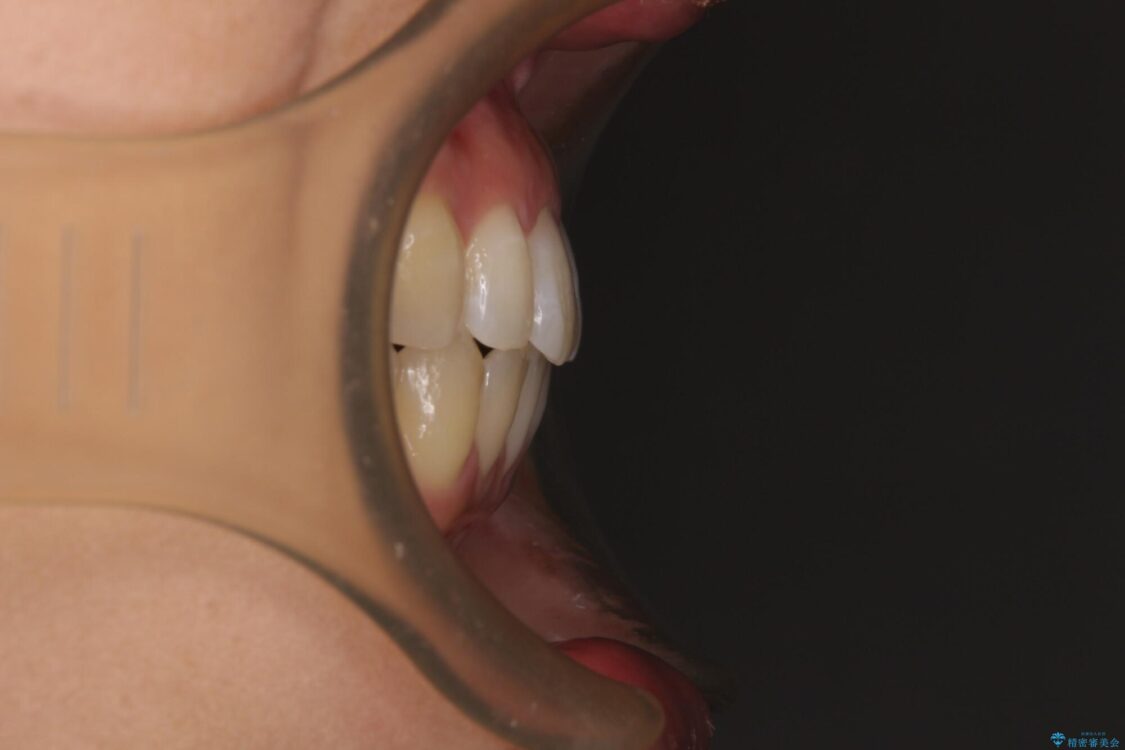

前歯の上下スペースと前歯の隙間を気にして来院された患者様です。

飲み込みや話をするときに舌を突出させる癖が強くあり、それが原因でスペースが空いていました。

治療前

• 隙間だらけの歯列 インビザラインで改善 治療前画像